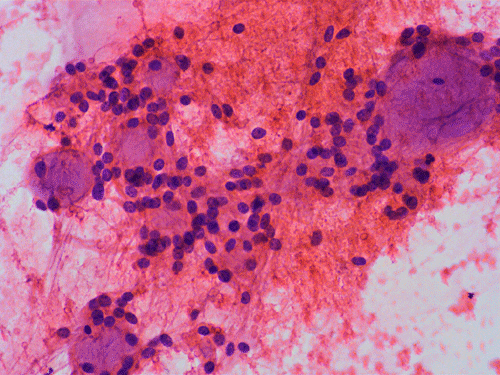

Clinical informationThe patient was a 40 year-old man with back pain for a long but unknown duration of time. MRI revealed a sharply circumscribed, lobulated, brightly enhancing, 3 cm mass in the cauda equina. The mass was removed and the followings are representative photomicrographs from the specimen. Panel A to C are taken from intraoperative cytologic preparation, D and E are taken from frozen section, F to H are taken from permanent sections.

On cytologic preparations, there are clumps of tissue that do not smear out well (Panel A). On higher magnification, these tissue clusters are composed of large blobs of bluish, acellular, mucoid material admixed with cells with relatively uniform, bland nuclei and small amount of cytoplasm (Panel B). In the less tightly packed areas, the long cytoplasmic processes of the cells can be well appreciated (Panel C). These long processes are highly suggestive of a glial neoplasm. On frozen sections, the lesion is composed of multiple blobs of bluish, mucoid material surrounded by tumor cells (Panel D and E). Features of the paraffin sections are not that much different from that of the frozen sections (Panel F G H).